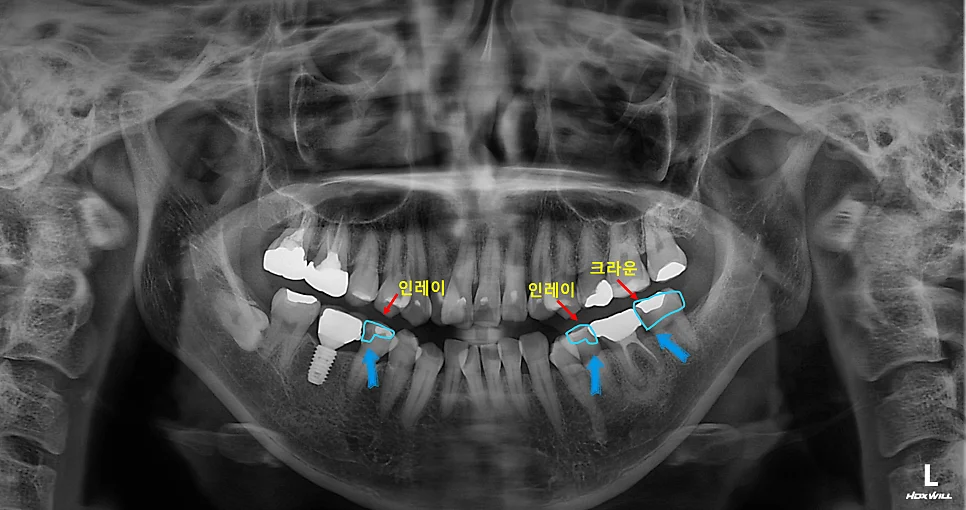

좋은 진료를 정직하게 | 선한 영향력으로 더 나은 가치를 사랑니 때문에 앞어금니 신경치료? 4개 발치와 충치 치료 전 과정 강서구 마곡 서울쏙쏙치과 사랑니 발치 + 신경치료 + 크라운 + 인레이 증례 안녕하세요^^ 좋은 진료를 정직하게, 선한 영향력으로 더 나은 가치를 전하는 강서구 치과 서울쏙쏙치과 꿈꾸는 쏙쏙 치과의사 박상억입니다. 오늘은 사랑니 발치와 그 바로 앞 치아의 … 더 읽기